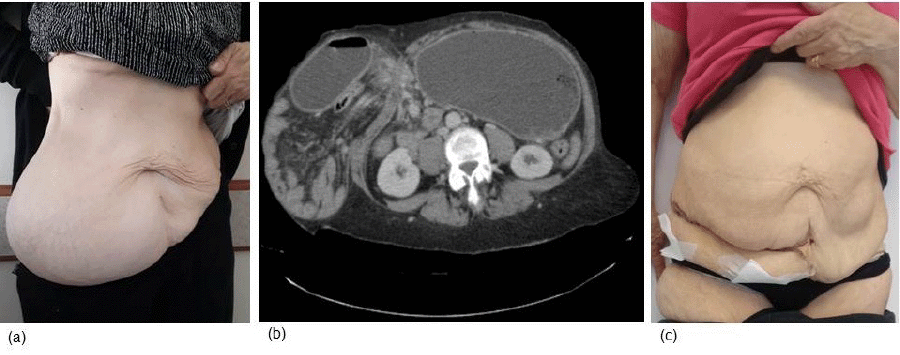

The treatment of Spigelian hernia consists of surgery.6 Hernioplasty is typically accomplished with a transverse incision and mesh repair.7 An open or laparoscopic approach may be used based on the surgeon's expertise.8,9 A 57-year-old female presented to our emergency department with a 72-hour history of abdominal pain, nausea, and bilioenteric vomit. Her medical history was dominated by overweight (BMI = 29) and hypertension. She referred to a bulging mass in the abdomen for 15 years without previous manifestations. Physical examination revealed a well-developed female in acute distress due to abdominal pain. An abdominal exam showed a distended abdomen and a big bulging mass in the right lower quadrant with tenderness and the impossibility of obtaining complete manual reduction (Figure 1A). Blood exams just revealed hypokalemia.

The patient underwent an abdominal CT scan, revealing a Spigelian hernia in the right lower quadrant, with bowel loops, colon, and stomach introducing into a large defect (230.0 × 220.0 × 168.8 mm; thickened abdominal wall muscles and Tanaka index of 41%) (Figure 1B).

Figure 1. Spigelian Hernia Treatment Process. Published with Permission

A) Preoperative Physical Examination; B) CT Scan; C) Physical Examination One-Week Postoperative

Two weeks after hospital discharge, the patient was admitted for elective surgery. Laparotomy was performed with a transverse incision over the bulging mass in the right abdomen. Once the hernia sac was identified, it was isolated from subcutaneous tissues and the musculofascial plane. Muscles were found weakened and thickened. After opening the hernia sac, the content (mainly small bowel) could be gradually reduced into the abdominal cavity, showing a 7 cm wall defect on the fascia. After checking that the omentum would separate abdominal content from the polypropylene mesh, we decided on an intraperitoneal repair technique. The mesh was fixed with a transmuscular PDS 1 suture. We closed the peritoneum and muscular plane above the mesh, and the surgical procedure ended with positioning two subcutaneous drains and wound closure. The patient was discharged on postoperative day 3 (Figure 1C). No major complications or recurrence were reported after two years of follow-up.